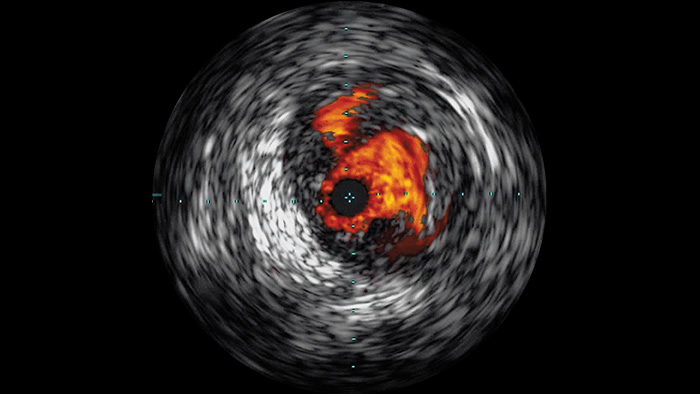

A ecografia intravascular (IVUS) é uma tecnologia de imagem baseada em cateter que permite aos médicos visualizar vasos sanguíneos de dentro para fora para auxiliar na avaliação da presença e extensão da doença. A IVUS ajuda a decidir, orientar e confirmar o tratamento de intervenção correto para cada paciente.

Visualiza imagens de alta definição de vasos com detalhes vasculares impressionantes para apoiar estratégias de tratamento, navegação e acompanhamento precisas.